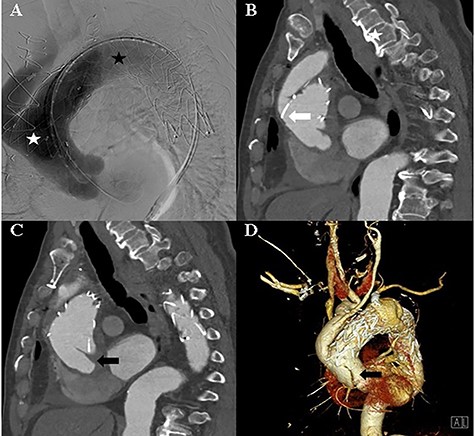

The patient remained asymptomatic with stable vital signs. A scheduled computed tomography was performed after 1 week. Computed tomography revealed a newly localized intimal dissecting flap at the proximal ascending aorta, which was located proximally, extending to the ostia of the right coronary artery. The patient underwent an emergency open repair operation. Circulatory arrest was established at a rectal temperature of 20°C, and cerebral perfusion was accomplished through the 18-mm graft cannula and left femoral artery cannulation. During gross examination, the 18-mm graft was seen detached from the ascending aorta, which was opened longitudinally, and an intimal tearing site was identified (Fig. 3). The dissection occurred transversely at the proximal stented site and was extended up to the sinotubular junction around the left coronary sinus and near the right coronary orifice in the right coronary and non-coronary sinuses. A Gelweave 28-mm straight graft was used, which was connected to the proximal aorta and reinforced with the double sandwich technique (Fig. 3). The distal anastomosis was performed, including a proximal resected valiant stent graft and the patient’s native aorta with a Teflon felt by sandwich technique. After the operation, the patient remained asymptomatic.

A: Intraoperative view of the transected ascending aorta due to the thoracic stent graft (black asterisk). B: The post-operation computed tomography image shows the replaced ascending aorta (white asterisk).